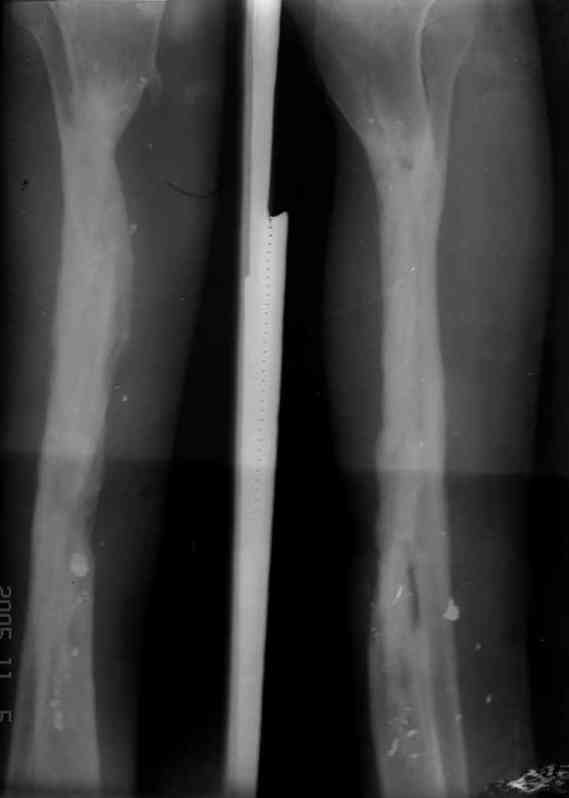

5. Ну и чтобы не быть голословным. Молодой человек подорвался на фугасе (Чечня, 2005 год). Свежие рентгенограммы:

Соответственно ожоги и дефект мягких тканей, переломы костей стопы и пр. Наложили аппарат

Реализовал описанную выше методику, и в итоге вот что получилось. Высылаю лишь прямые проекции,

в боковых тоже всё в тему.

Сейчас аппарат сняли, но случай ещё не завершенный.

Признаюсь честно, не совсем уверен в прочности консолидации на стыке косточек. Кроме того, укорочение в районе 6 см. Сейчас реабилитация - ходит опираясь на ногу с одним костылем.